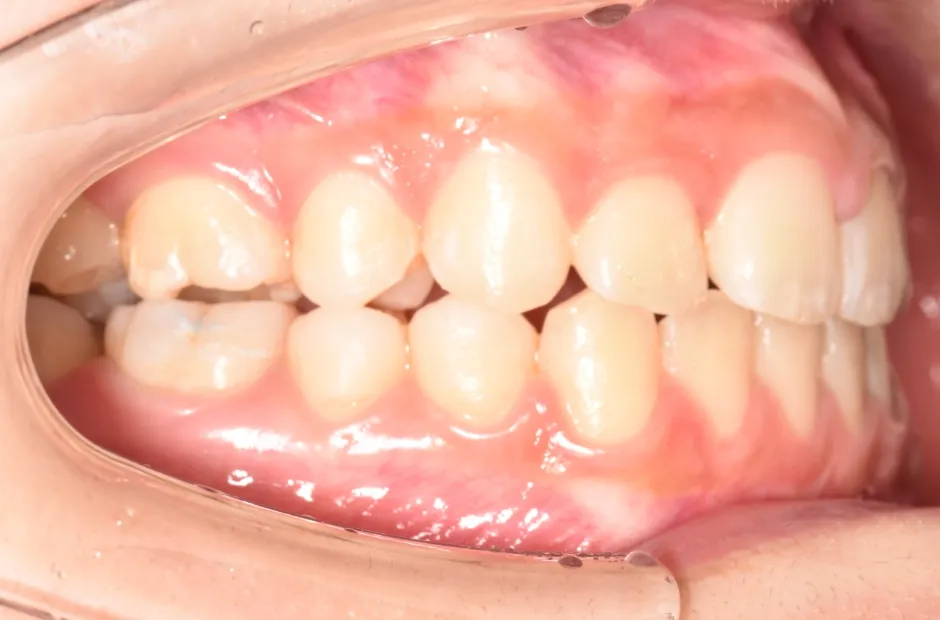

叢生

| 診断名・主訴 | 叢生 |

|---|---|

| 年齢・性別 | 43歳・女性 |

| 治療期間・回数 | 2年7か月 27回 |

| 治療に用いた主な装置 | 舌側矯正 |

| 抜歯部位 | 両顎4,4 |

| 治療費 | 100万円(税抜) |

| リスク・副作用 | 装置による違和感・疼痛・歯肉退縮・歯根吸収・虫歯のリスクなど |

治療前